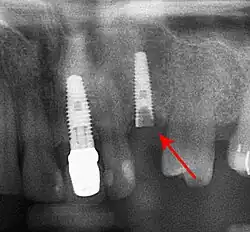

Bone loss (peri-implantitis) on implants over 7 years in a heavy smoker

Screw fracture

Fracture of abutment screws (arrow) in 3 implants required removal of the remainder of the screw and replacement.

Dental cement under the gingiva causes peri-implantitis and implant failure.

Beyond the possibility of mechanical failure[98] which may be due to poor prosthetic fitment, wear and tear, or user-induced actions such as bruxism, dental implants are also subject to peri-implant mucositis and peri-implantitis, where gum tissue and bone mass around the implant are resorbed, and the implant gradually becomes loose, and has to be removed.[99][100] In addition, although titanium is generally well tolerated by the body, there have been cases where the build-up of titanium particles released by the implant may cause systemic inflammatory response.[101] Because there is no dental enamel on an implant, it does not fail due to cavities like natural teeth. While large-scale, long-term studies are scarce, several systematic reviews estimate the long-term (five to ten years) survival of dental implants at 9398 percent depending on their clinical use.[15][16][17] During initial development of implant retained teeth, all crowns were attached to the teeth with screws, but more recent advancements have allowed placement of crowns on the abutments with dental cement (akin to placing a crown on a tooth). This has created the potential for cement, that escapes from under the crown during cementation to get caught in the gingiva and create a peri-implantitis (see picture below). While the complication can occur, there does not appear to be any additional peri-implantitis in cement-retained crowns compared to screw-retained crowns overall.[102] In compound implants (two stage implants), between the actual implant and the superstructure (abutment) are gaps and cavities into which bacteria can penetrate from the oral cavity. Later these bacteria will return into the adjacent tissue and can cause periimplantitis.